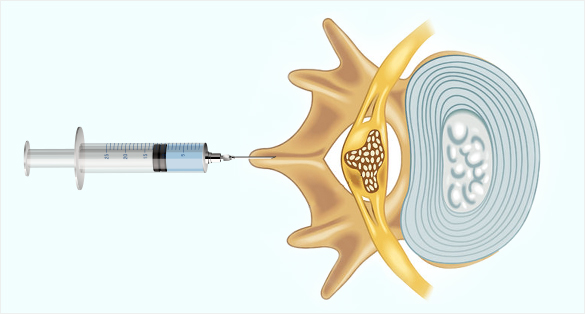

경막외 신경치료

디스크 치료에 가장 기본이 되는 신경치료입니다.

경추 경막외 신경치료

경추 5/6번 경막외 공간에 약물을 주입,

신경줄기로 잘 퍼지는 모습 -